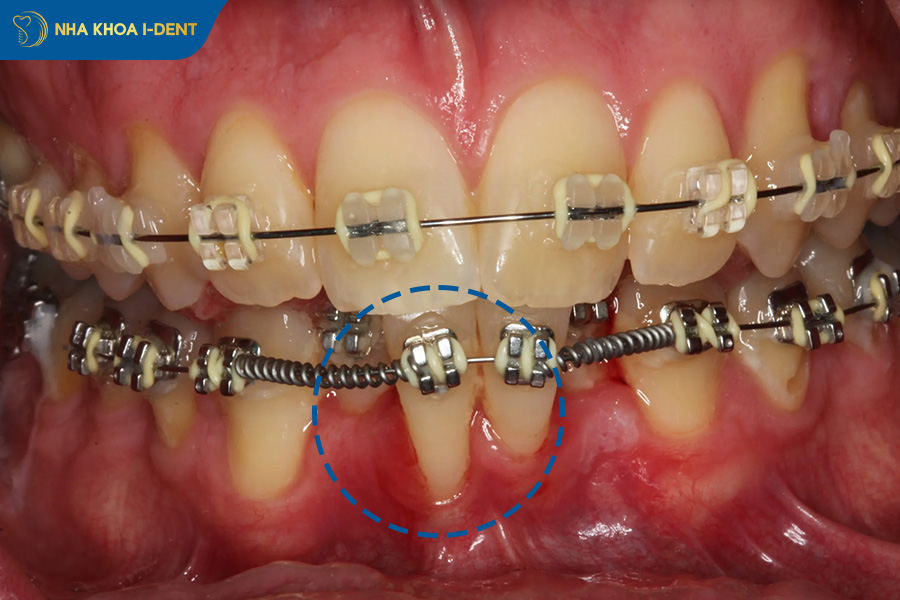

1.6. Gắn mắc cài sai

Gắn mắc cài sai có thể khiến toàn bộ hướng di chuyển răng lệch khỏi kế hoạch, từ đó kéo theo hàng loạt sai số trong suốt quá trình chỉnh nha.

Vì mắc cài là bộ phận quyết định phần lớn hướng lực tác động lên từng răng. Chỉ cần vị trí dán mắc cài không chuẩn, độ torque hoặc angulation không đúng sẽ làm răng di chuyển lệch hướng khác với mong muốn, làm sai khớp cắn, lệch đường giữa hoặc khiến răng đổ nghiêng thay vì di chuyển chuẩn.

Bệnh nhân khó tự xác định bác sĩ có gắn mắc cài sai hay không, nhưng có thể đến nha khoa để kiểm tra lại khi một vài răng di chuyển bất thường so với cả cung hàm, mắc cài bong lệch liên tục hoặc kết quả từng giai đoạn không khớp mục tiêu bác sĩ đã tư vấn ban đầu.

Gắn mắc cài sai khiến toàn bộ hướng di chuyển răng lệch khỏi kế hoạch chỉnh nha.